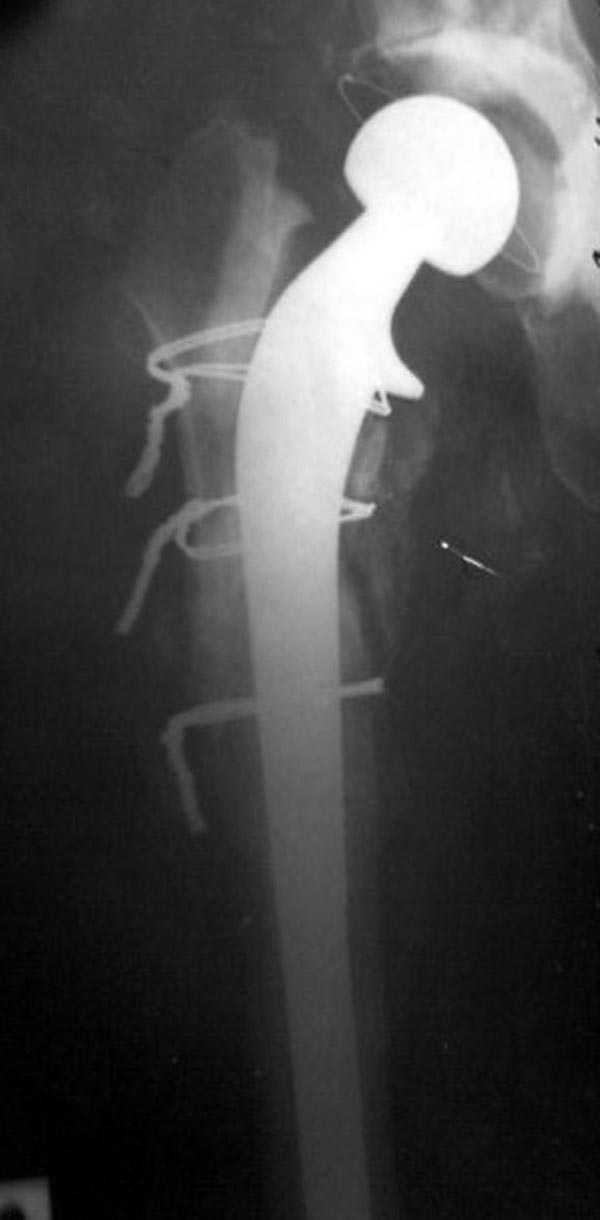

Вот снимки по свежей ситуации, парень 19 лет, длинный оскольчатый перелом бедра от шейки до в-с/3. давно уже ходит на своих ногах.

Делалось не мной (ассистировал), я на тазах "пока ещё не волшебник, а только учусь"

Представленные Вами рентгенограммы действительно являются примером качественной фиксации спице-стержневым аппаратом. Они, как ни что другое, многое иллюстрируют.

Кроме того, было бы ошибкой ставить знак равенства между нашим и Вашим пациентами. Они не только не похожи, разница между ними просто огромная. Говорю это не для того, чтобы задеть Вас или обидеть. Ни в коем случае. Просто теперь я понимаю, что Ваше мнением строится на простом преломлении Ваших подходов к лечению пациентов со свежими переломами, на ситуацию, абсолютно несопоставимую, подобную нашей.